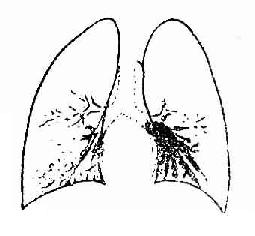

(二)支气管造影

正常支气管显示规则的树枝状,逐渐分支,越分越细,管壁光滑整齐。支气管扩张的造影所见可分为柱状、囊状及混合型三种类型。柱状支气管扩张表现为管腔呈圆形或杵状,远端稍大。并发肺不张时,扩张的支气管可有聚拢现象。囊状支气管扩张表现为支气管未端呈多个扩张的囊,状如一串葡萄(图3-17A,B)。造影剂常部分充盈囊腔,在囊内形成液面状与囊状同时并存,是为混合型,病变往往比较明显而广泛。

图3-17B 左下柱状支气管扩张造影所见